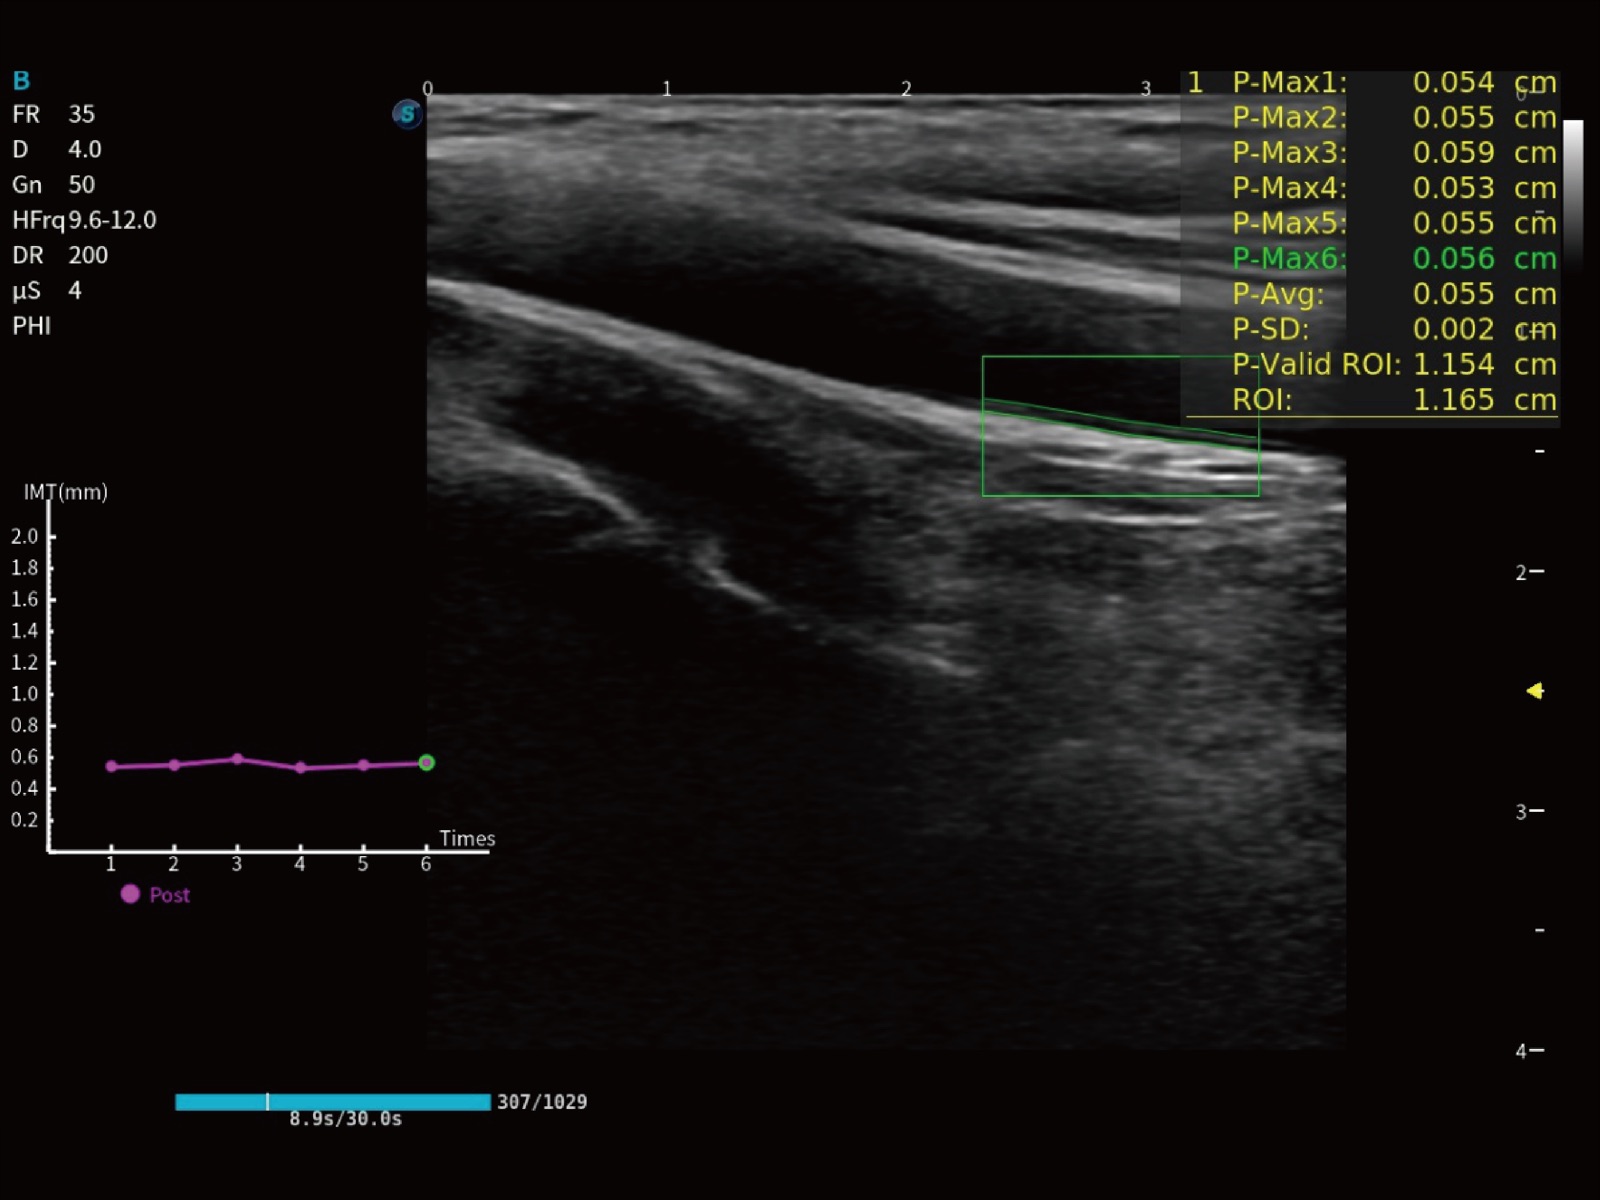

作为开立医疗全新打造的高端床旁笔记本超声,E11不仅具备卓越的图像质量,同时搭载全面高效的自动测量工具,助力医生实现更快速、更精准的床旁诊断。

E11搭载了丰富的自动化测量工具,以及专为POC科室定制的高级功能;同时配备了为急诊医师量身打造的 SonoFast急重症超声流程,以帮助临床医生最大限度的提升工作效率